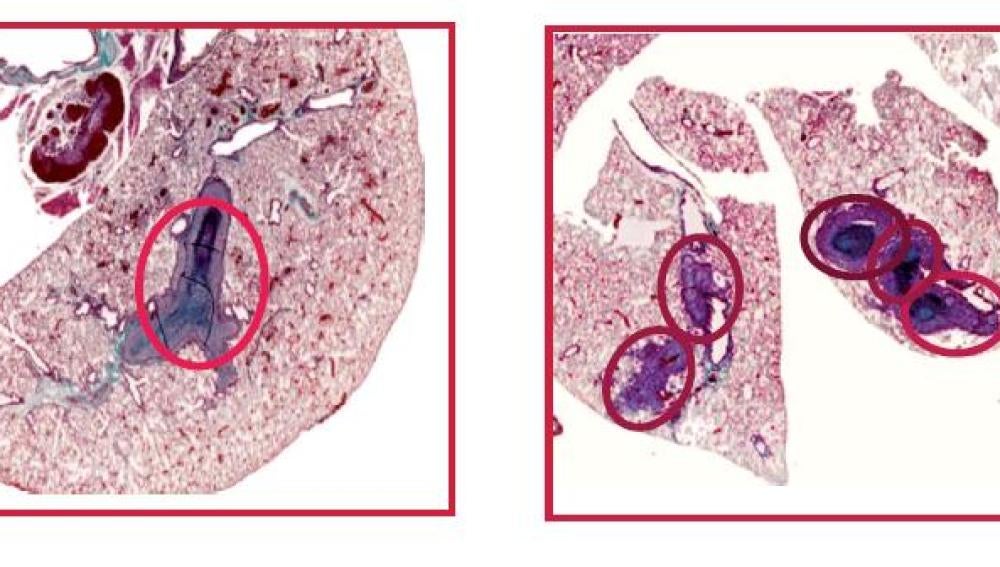

Ahora, un equipo de científicos españoles ha demostrado que, en ausencia de NCoR, los tumores adquieren mayor tamaño y son más invasivos. Los resultados, obtenidos mediante xenotransplantes en ratones inmunodeprimidos, han sido publicados en la revista PNAS.

“Los efectos observados en ausencia de NCoR se correlacionan con un aumento de la transcripción de un conjunto de genes prometastásicos que aumentan la malignidad de los tumores y disminuyen la supervivencia de los pacientes de cáncer”, afirma Ana Aranda, que dirigió el trabajo desde el Instituto de Investigaciones Biomédicas “Alberto Sols”, centro mixto UAM-CSIC.

El descubrimiento de NCoR ha resultado esencial para mediar los efectos antitumorales y antimetastásicos del receptor de hormonas tiroideas TRb; efectos que fueron descritos, en un trabajo previo, por el equipo que dirige Ana Aranda.

“La relevancia de estas observaciones para los tumores humanos se pone de manifiesto por el hecho de que la expresión de NCoR y TRb está reducida significativamente en los hepatocarcinomas y en los tumores de mama más agresivos”, señala la investigadora.